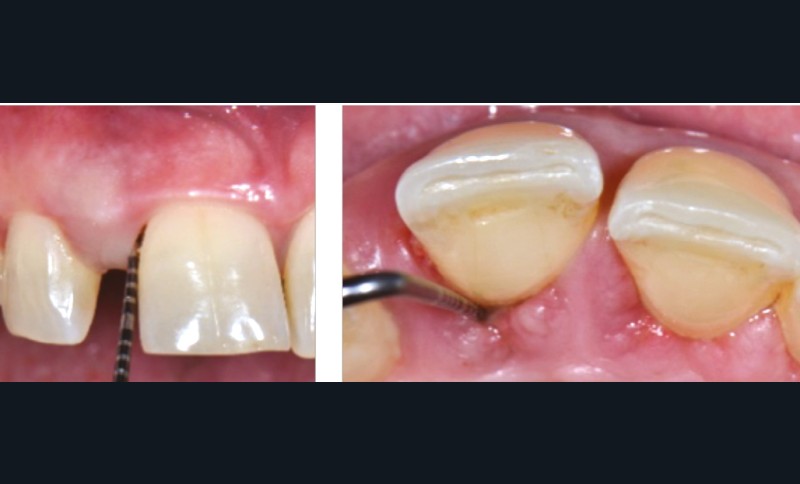

L’étiologie des MDP est complexe et souvent multifactorielle. L’inflammation du parodonte (et son élargissement desmodontal), mais surtout la perte du ligament et de l’os alvéolaire dans lequel il est attaché, diminuent la solidité de l’ancrage et la résistance de la dent à l’impact des forces en présence :

- occlusion naturelle ou traumatique (perte de dents avec ou sans effondrement occlusal postérieur, interférences occlusales) ;

- parafonctions (bruxisme, clenching, déglutition atypique…) ;

- fonctions orales : phonation, mastication, déglutition (pression exercée par la langue, les lèvres, les joues…) ;